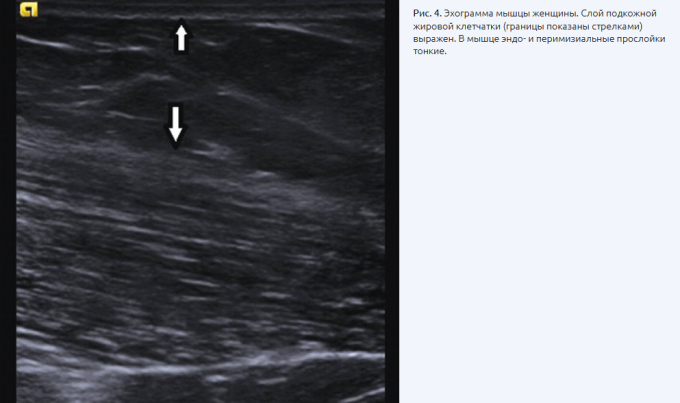

Вероничка-клубничка, самое информативное это УЗИ

УЗИ используется не только для диагностики внутренних органов и сосудов, но и для обследования мягких тканей кожи, подкожно-жировой клетчатки, мышц. То есть визуально видно, где мышца, где пжк. Есть исследование на состав тела.

Я делала, но в прошлом году. Возраст.